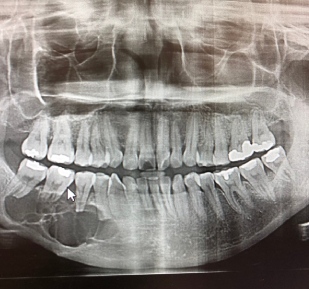

İstanbul Kent Üniversitesi Diş Hastanesi